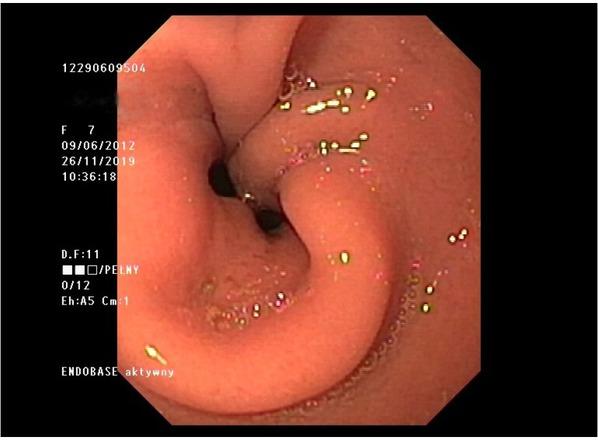

Figure 1